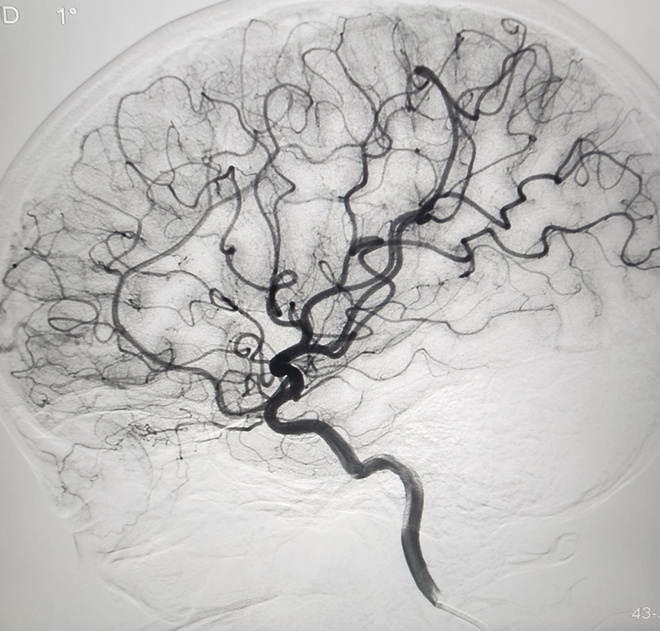

Sau 6 tháng đặt stent, túi phình trong động mạch cảnh của bệnh nhận đã tiêu biến.

Ca can thiệp nội mạch cho bệnh nhân P. diễn ra thành công. Bệnh nhân được xuất viện sau một ngày.

Tái khám vào cuối tháng 6, chị P. cho biết tình trạng đau đầu chấm dứt hoàn toàn. Kết quả chụp MRI cho thấy động mạch cảnh trong não bệnh nhân không còn túi phình.